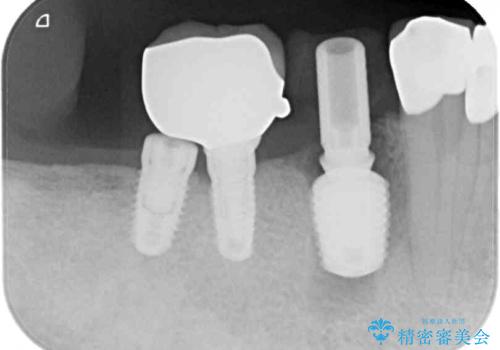

以前にも歯が割れてインプラント治療を行いましたが、抜歯してからインプラント埋入→仮歯装着までに半年以上を要し、その間に残された歯への負担が大きくなり、左右反対側のセラミッククラウンが破折したことがありました。

そのため、当院に新しく導入した手法により、抜歯をした日にインプラントを埋入し、そのままを仮歯を装着することで、他の歯への負担を軽減する計画を立てました。

インプラント埋入時に植立具合の安定性を測定したところ、十分な数値が得られたため、速やかに仮歯を装着して咬合回復をさせることができました。

抜歯を含めた外科処置を1回に抑えることができ、あっという間に治療を終えることができました。